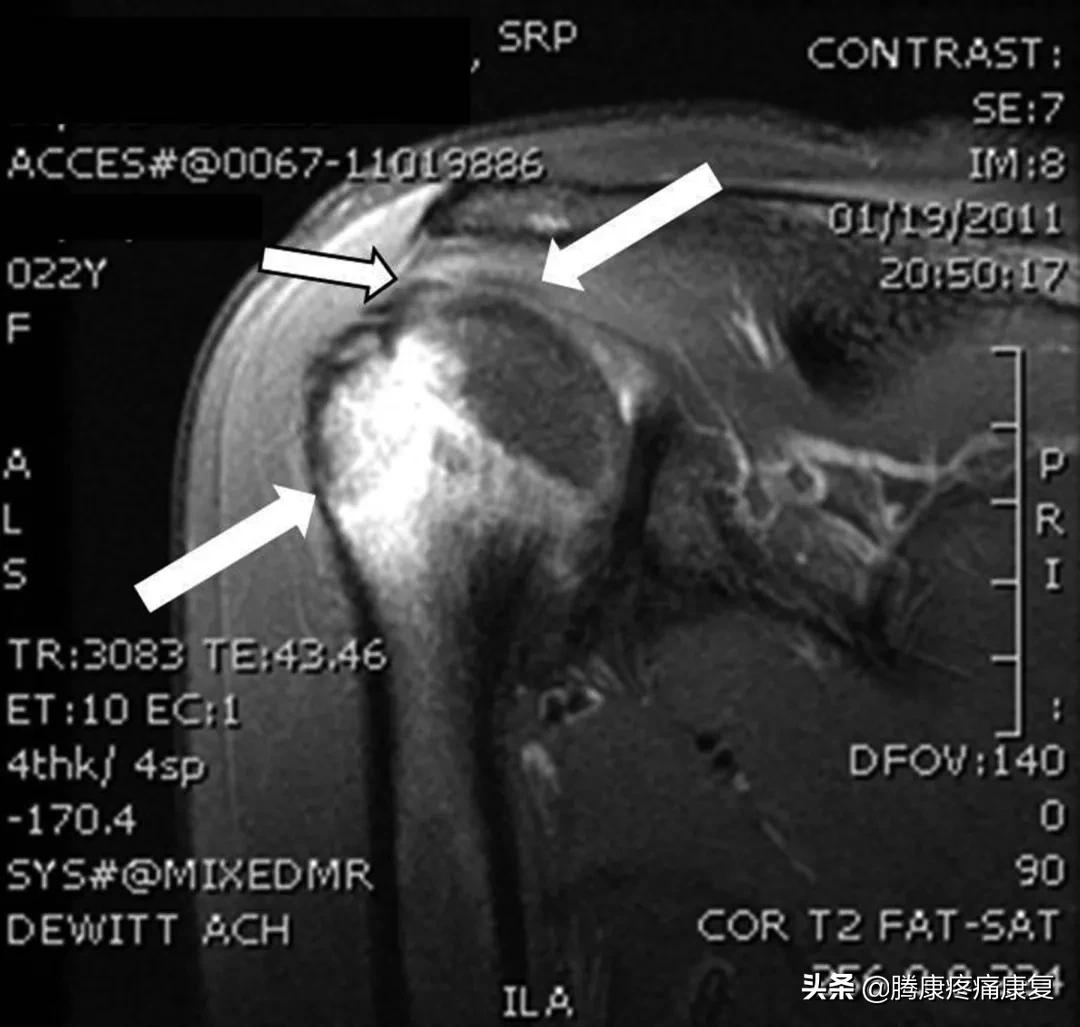

接种疫苗后8周的肩部T2加权MRI图像。左下箭头表示肱骨头皮质不规则。中上箭头表示冈上肌腱部分撕裂。右上箭头表示肩峰下囊积液。